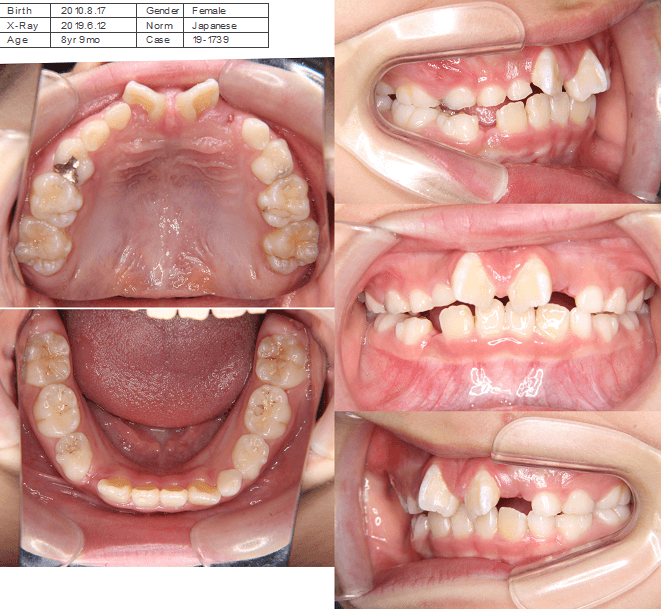

上歯前突+叢生症例 成長期

主訴 | 口元の突出感と歯並びが気になり、将来的な咬合状態を整える目的で来院された患者様です。 |

---|---|

診断結果 | 11歳1か月の女性。骨格的には日本人標準に近く、歯性の上顎前突および叢生が認められました。上下顎ともに歯列のスペース不足があり、永久歯の萌出や歯列の整列に支障をきたす可能性があると診断されました。 |

治療内容 |

|

治療後の経過 | 動的治療終了後は、上下顎の歯列が整い、口元の突出感と叢生が改善されました。審美的・機能的なバランスが取れた状態となり、現在は取り外し式リテーナーを使用し、保定期間に移行しています。 |

治療期間 | 動的治療期間:2年6か月 通院回数:25回 |

治療費用 | 720,000円 |